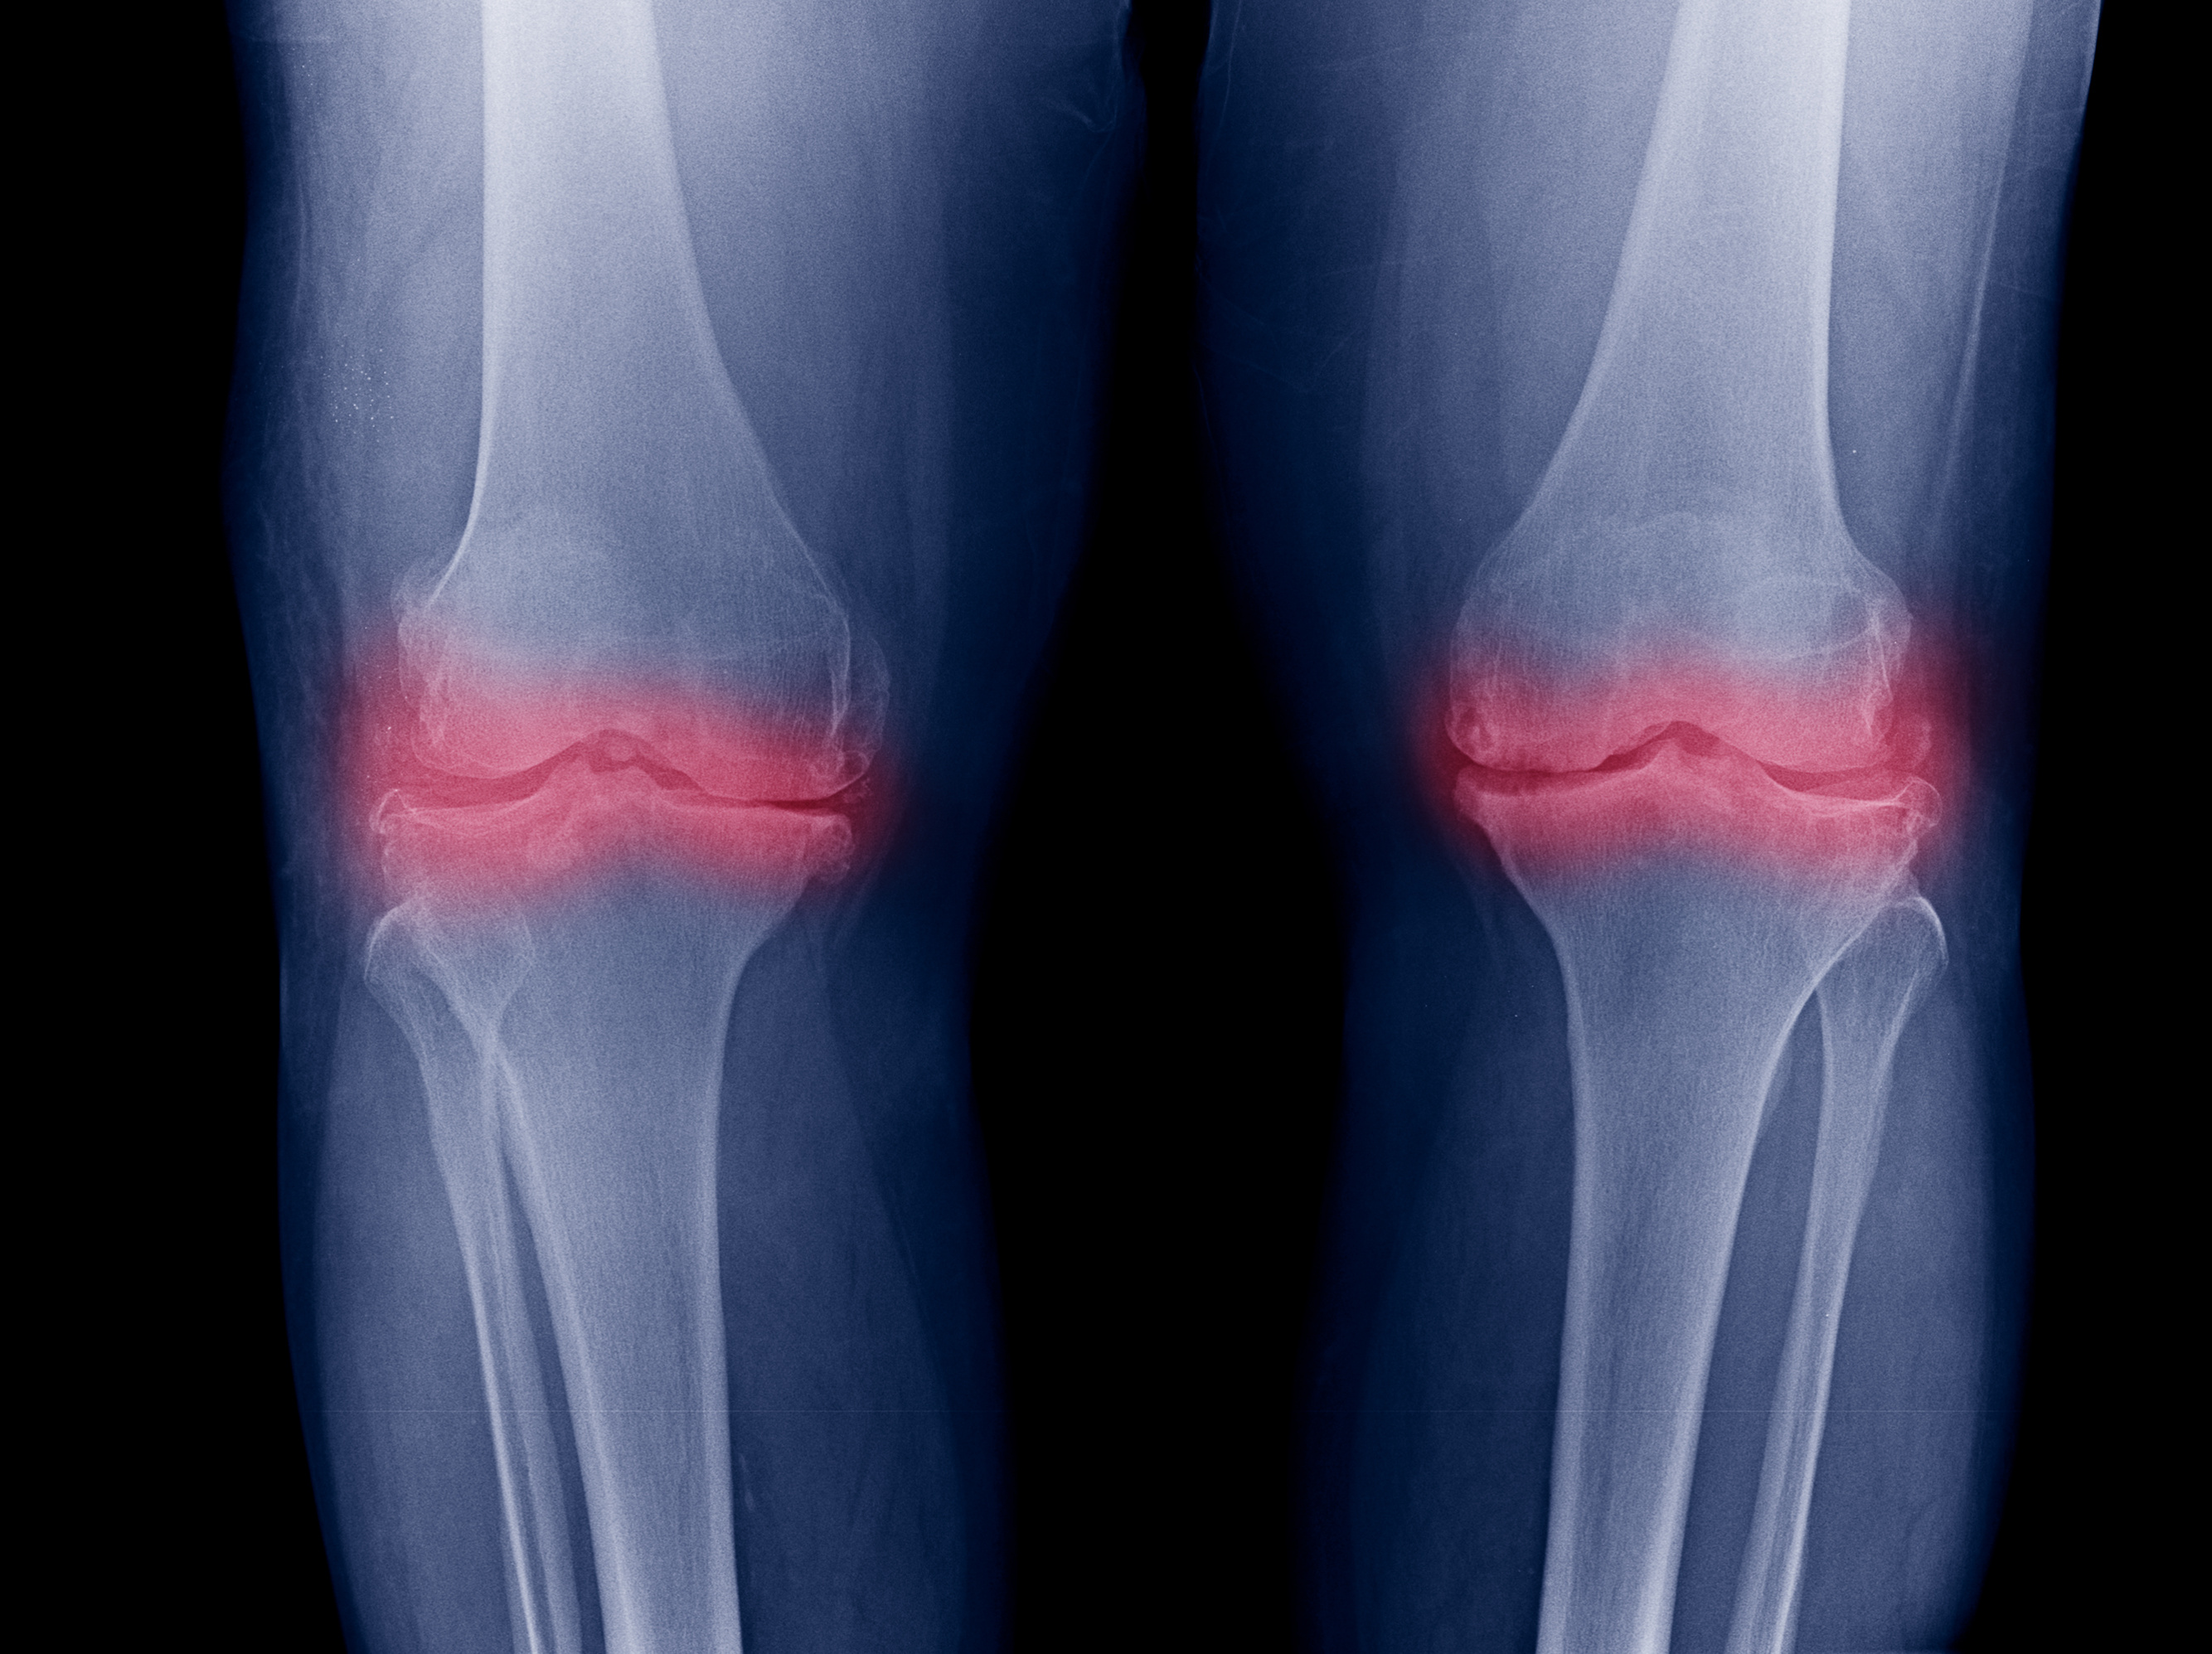

Most people don’t realize this, but millions of people have visible “damage” on X-ray or MRI with no pain at all.

Studies show that about 60% of adults over 50 (that’s 65 million Americans!) have a meniscus tear and feel fine. And close to 40% have a bulging disc in their spine without a single symptom. So if cartilage loss alone caused pain, all those people would be miserable. But they’re not.

Why X-Rays And MRIs Don’t Show The Whole Truth

Doctors are trained to look at structure. They see a scan that shows thinning cartilage, a torn meniscus, or a bulging disc…and immediately assume that’s the cause of your pain.